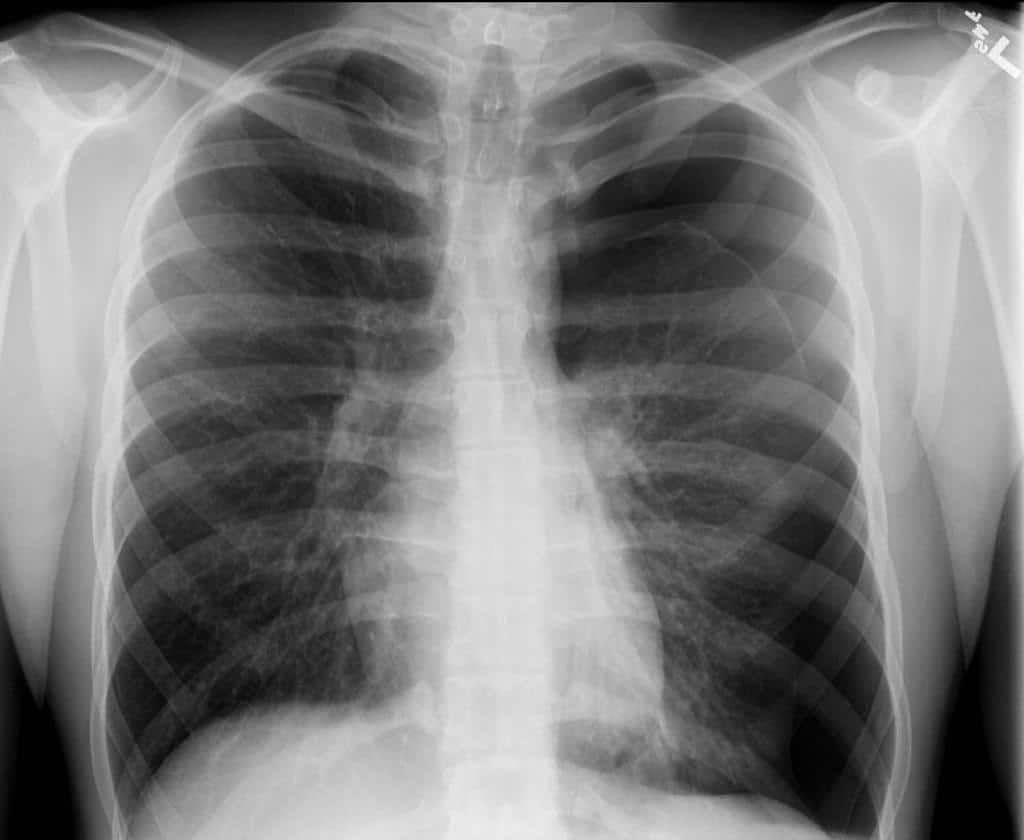

Tension pneumothorax is the result of a chest wound that allows air to enter but not escape the pleural space. Patients may have PEA, VF, or asystole. Often, a patient with tension pneumothorax will be one that is difficult to ventilate with uneven breath sounds and chest rise that is not symmetrical. The treatment is prompt needle thoracotomy and placement of a chest tube.

Tension Pneumothorax in Left Lung